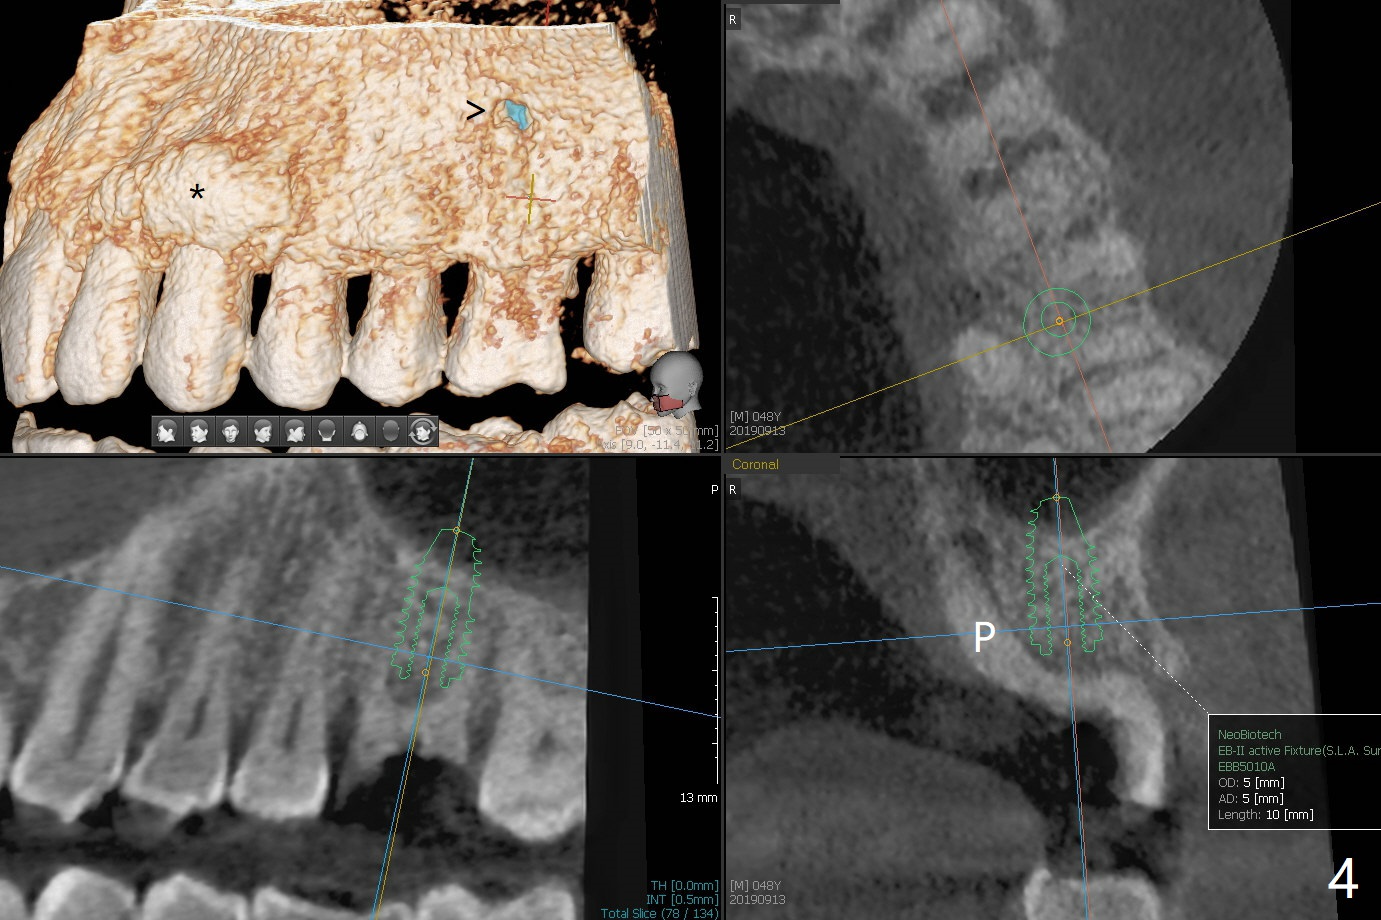

A 48-year-old man returns for implant at #14 after endo consult (Fig.1). The tooth appears to have fractured subgingival palatal (Fig.2,3 P). The furca is thin (Fig.3 *). A 5x10 mm implant will be placed slightly away palatal because of bone loss (Fig.4). Since the mesiobuccal (Fig.5 MB) and distobuccal (DB) sockets are close to the osteotomy (green), gauze with 1:50,000 Epinephrine (to reduce hemorrhage during sinus lift) will be placed away from the osteotomy (Fig.6 white area). In fact socket shield is conducted palatal.